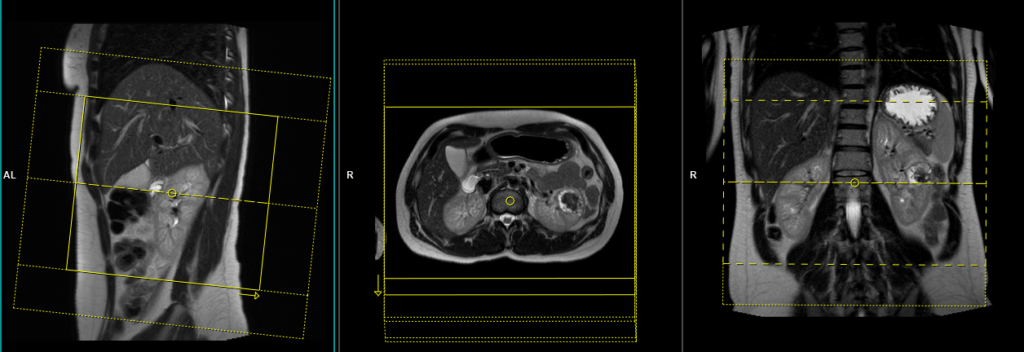

T2 tse\haste breath hold 4mm axial

Plan the axial slices on the coronal plane; angle the position block parallel to the right and left renal pelvis. Check the positioning block in the other two planes. An appropriate angle must be given in the sagittal plane (perpendicular to the long axis of kidney). Slices must be sufficient to cover both kidneys from two slices above the upper pole of kidneys down to two slices below the lower pole of kidney. Phase oversampling and, in the case of 3D blocks, slice oversample, must be used to avoid wrap around artefacts. Consider adding saturation bands at the top and bottom of the block to minimize artifacts caused by fat signal, arterial pulsation, and breathing. Instruct the patient to hold their breath during image acquisition.

When planning the axial breath-hold scans, it is crucial to utilize the breath-hold vibe coronal sequence. This is because during inhalation, the diaphragm exerts downward pressure on the liver, causing a shift in its position from the initial localizer scans. Therefore, to accurately capture the desired imaging area of the liver, it is important to account for this positional change by utilizing the breath-hold vibe coronal sequence.